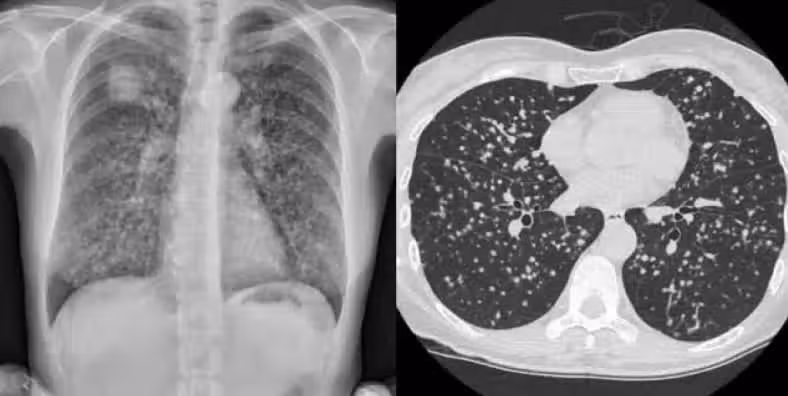

台灣家庭醫學科醫生陳昱彰分享了一個真實案例:一位60多歲女性患者在他的建議下,進行了低劑量肺部CT掃描,結果發現早期的肺癌。她告訴她的朋友們,大家也跟進做了檢查,最終又發現了另一例2期肺癌。儘管其中一位朋友非常抗拒檢查,但最終因肺癌離世。陳醫師建議,即便不是高風險群體,50歲以上的人也可以考慮自費進行低劑量肺部CT檢查,因為早期肺癌往往沒有明顯症狀,只有早期發現才能提高治療效果。

陳醫師在接受《中時新聞網》採訪時表示,這位60多歲女性患者一直是三高控制良好、定期就診的病人。多年前,她曾向陳醫師詢問還可以為健康做些什麼,陳醫師建議她嘗試地中海飲食、保持運動,並自費做一次全面的健康檢查,包括低劑量肺部CT、胃鏡和大腸鏡檢查。